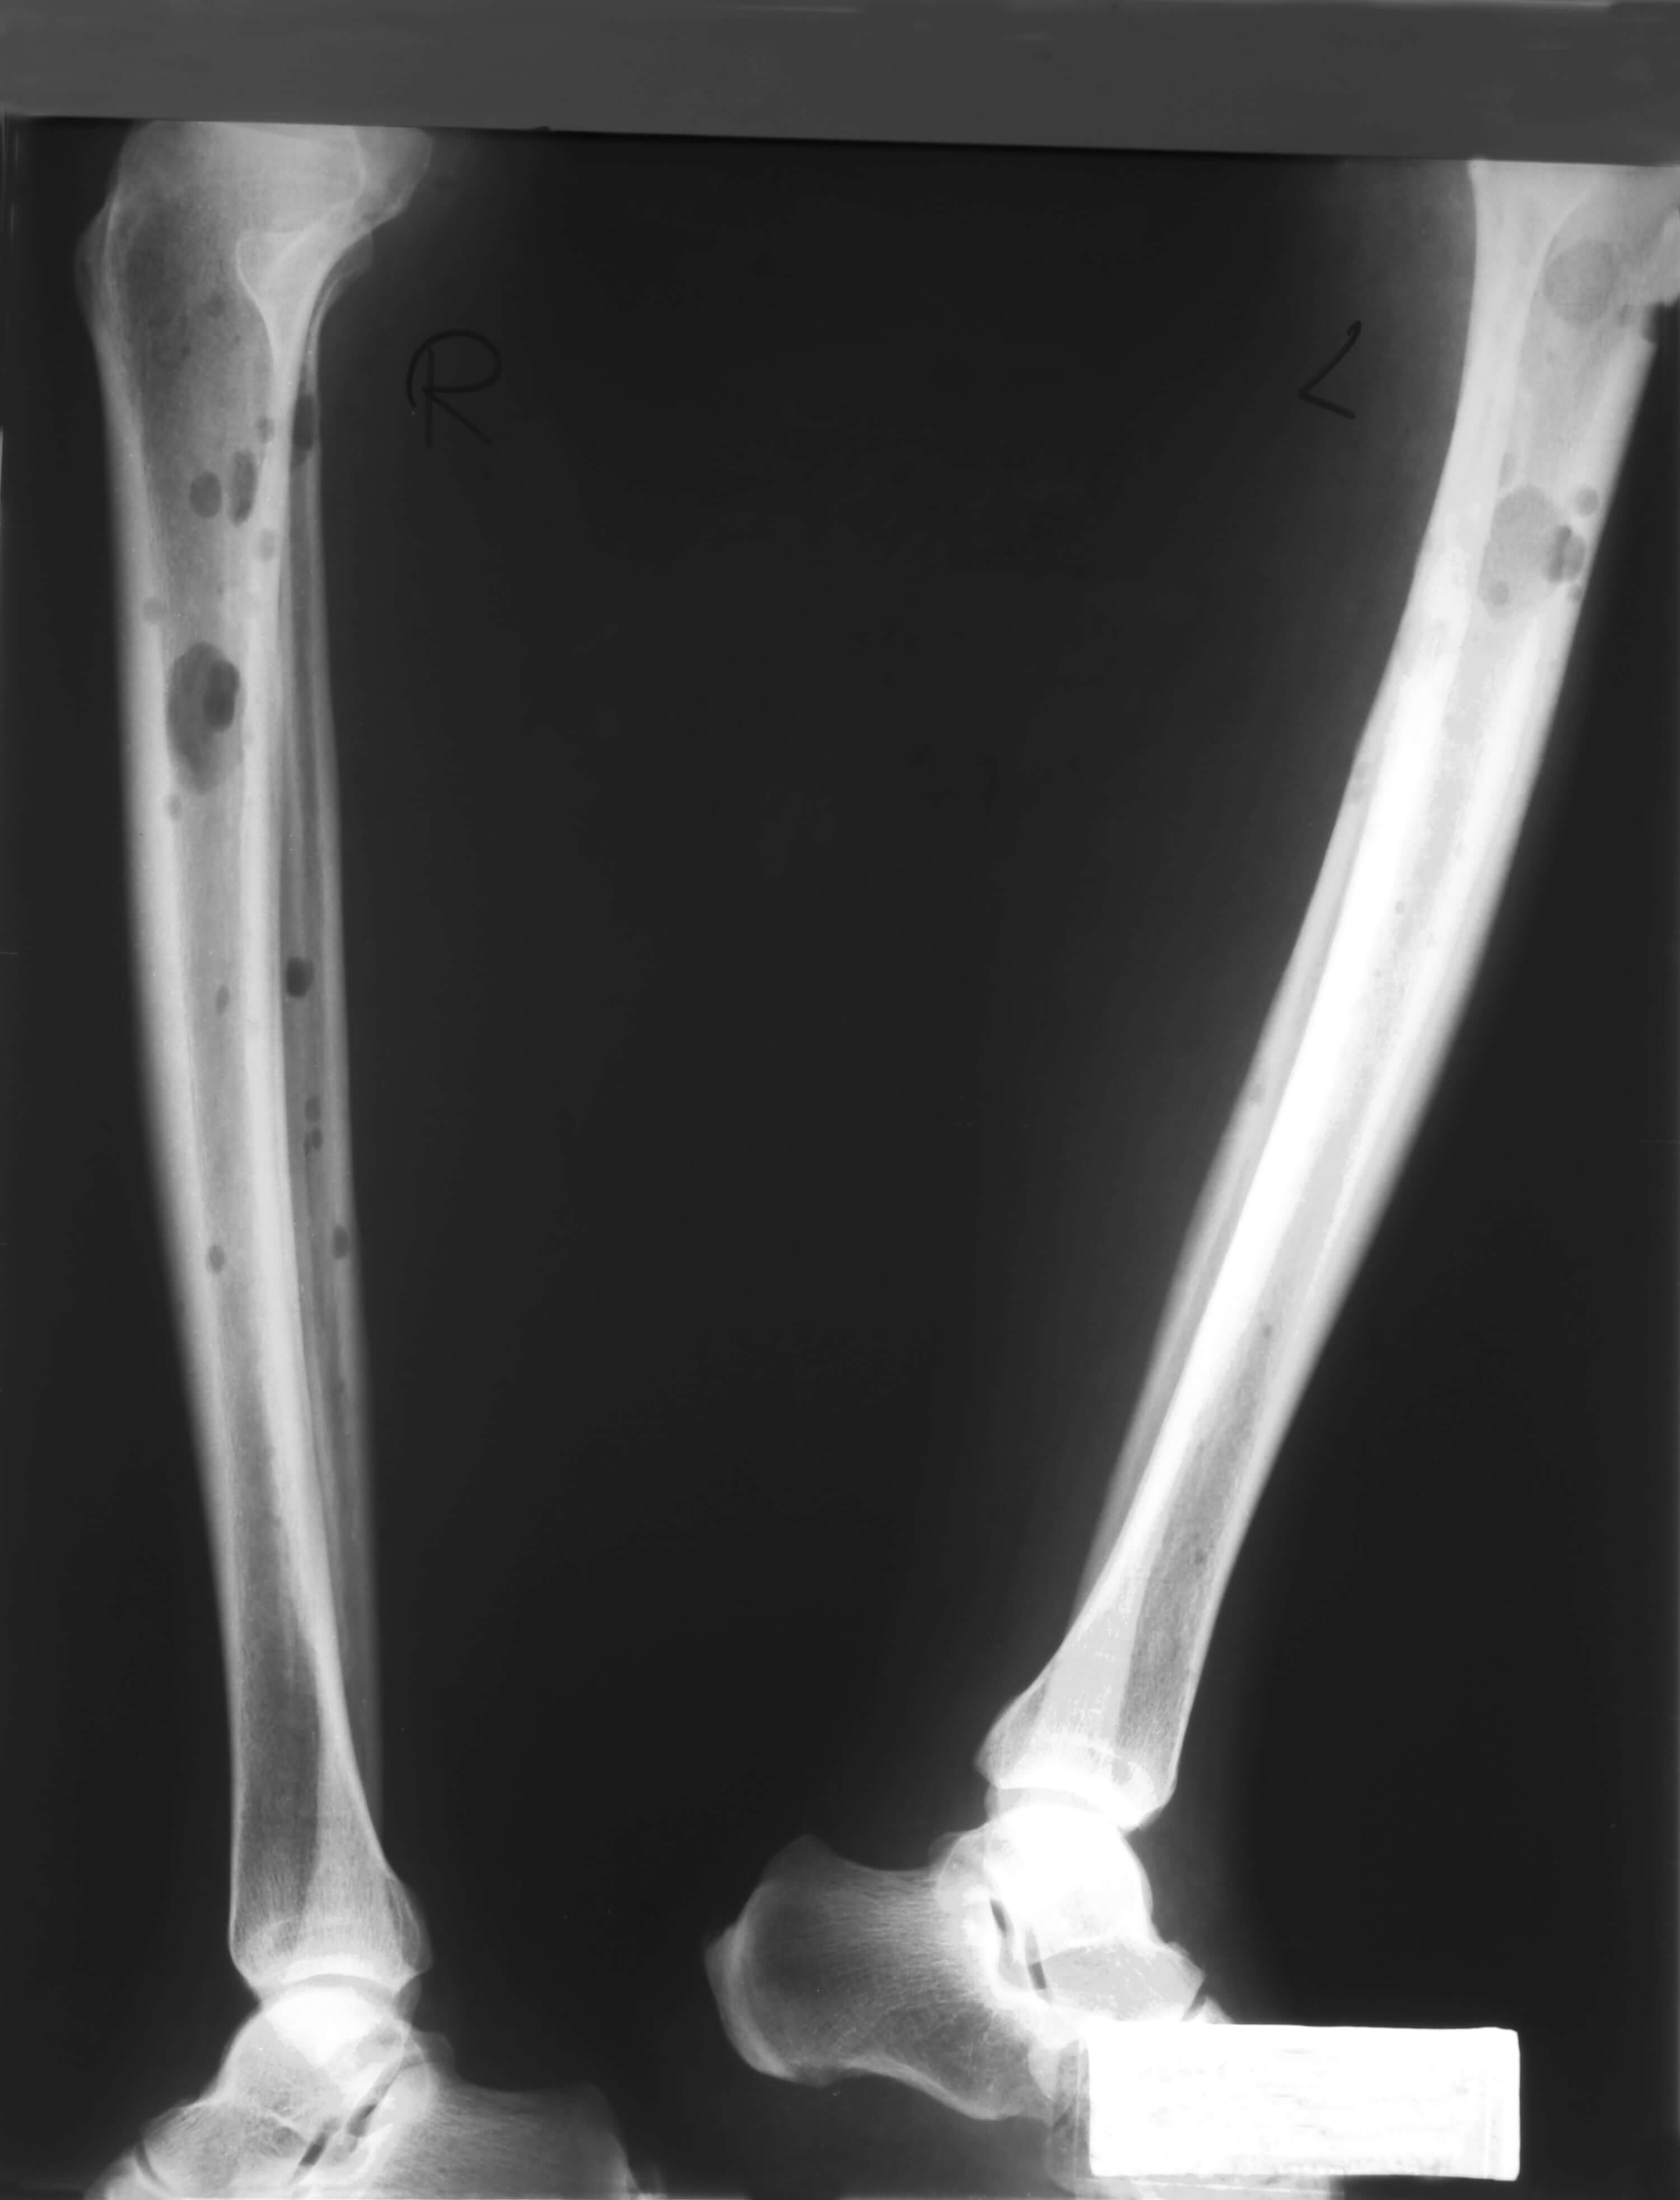

Остеодеструктивный процесс у больного множественной миеломой

Наиболее ранний и частый симптом – боли в костях (70% больных). Почему поражаются кости при множественной миеломе? В норме костная ткань находится в динамическом равновесии – слажено работают остеобласты (молодые клетки кости), и остеокласты (клетки, разрушающие костную ткань, растворяя минеральную составляющую костей). При множественной миеломе этот баланс нарушается. В костном мозге происходит повышенная выработка опухолевых плазматических клеток. Нормальная работа костной ткани при этом нарушается из-за продукции различных активных молекул, остеокласты начинают разрушать костную ткань, а остеобласты подавляются и не работают. Развиваются деструкции в костях (от лат. destructio – разрушение). На рисунке ниже представлен массивный остеодеструктивный процесс в костях позвоночника.

Чаще деструкции развиваются в плоских костях (череп, таз, грудина, ребра, позвонки), проксимальных отделах длинных трубчатых костей (плечевых, бедренных). Вследствие того, что кости становятся ломкими, истонченными, происходят патологические переломы костей. Перелом называется патологическим, если он произошел в зоне патологической перестройки кости. Он случается от травмы, неадекватной по силе (подъем незначительного груза, переворот во сне, резкое движение), или же может произойти в покое. Часто при миеломе возникают компрессионные переломы позвонков, они могут привести к сдавлению спинного мозга, параличу.

Инструментальные методы исследования необходимы для того, чтобы обнаружить повреждение костей, характерное для миеломы – деструкции, переломы, новообразования (плазмоцитомы). Есть несколько методов исследования: рентгенография, КТ, МРТ.